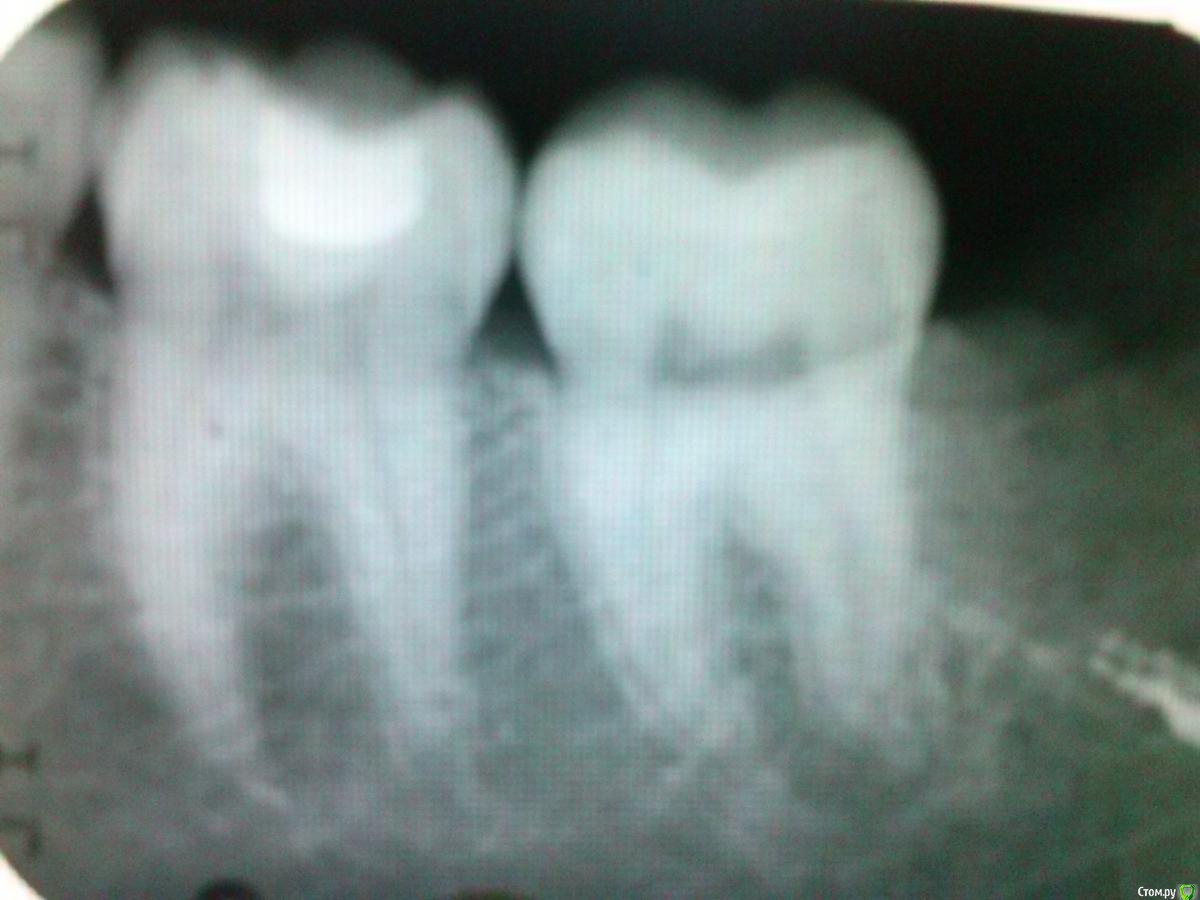

Tatyanka Опубликовано 9 января, 2015 Поделиться Опубликовано 9 января, 2015 (изменено) Здравствуйте, уважаемые фанаты своего дела, помогите разобраться в ситуации.В начале декабря обратилась к стоматологу с ноющей болью в районе 4.6-4.7. Оба зуба запломбированы - был кариес. 4.7 было решено перепломбировать, после чего доктор направил меня на рентген - заподозрил дистопию и ретенцию 4.8. Опасения подтвердились - зуб лежал в десне и упирался в 7, решили, что именно он был причиной боли, восьмерку удалили. И вот уже месяц не могу жить без "Кетанова": днем боль терпимая, не постоянная - приступами, к вечеру/ночи становится очень сильной. Первый врач утверждает, что это последствия сложного удаления, после праздников обещал направить на физио-лечение. Второй (тот, что удалял 8) после осмотра сказал, что лунка уже благополучно зажила и болеть не может, это пульпит, вопрос только - какого зуба (либо 6, либо 7)? Сделала снимок 4.6-4.7, врач сможет принять только в понедельник Второй день держится температура ок. 37,2. Так что же это все-таки: пульпит или последствия удаления? Как дожить до понедельника - нужно ли что-нибудь принимать, полоскать?PS прошу прощения за качество снимка. Изменено 9 января, 2015 пользователем Tatyanka Ссылка на комментарий

shishok Опубликовано 9 января, 2015 Поделиться Опубликовано 9 января, 2015 В 46 пломба близко прилегает к пульпе.Неплохо бы сделать ОПТГ,может дело и не в нижних зубах. 1 Ссылка на комментарий